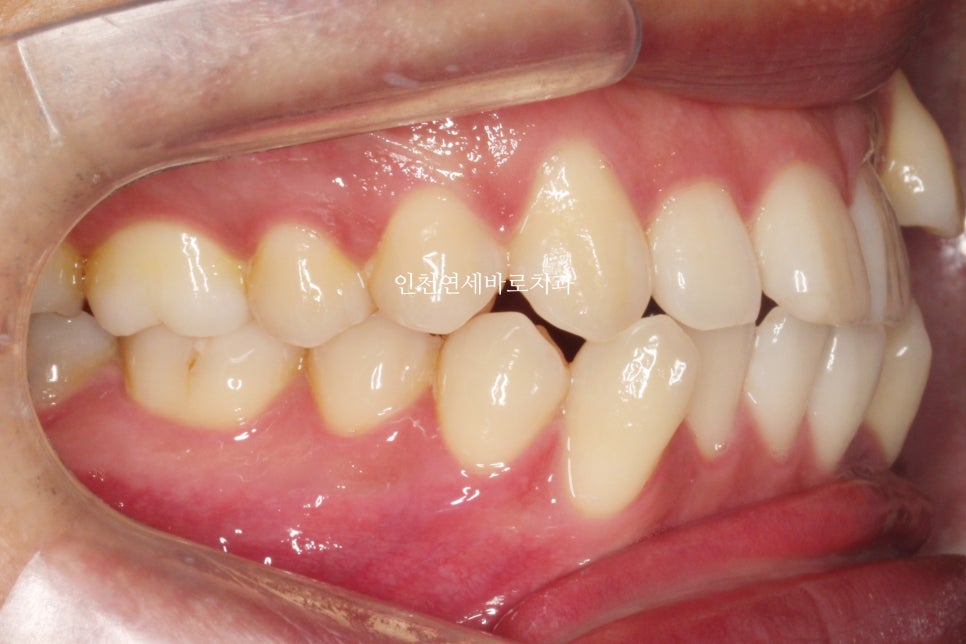

발치 교정으로 인비절라인 끝난 환자분으로

오른쪽은 그냥 돌출입의 교정

왼쪽은 덧니의 발치교정으로

좌 우를 보면 인비절라인과 관련된 모든 발치교정 이야기를 할 수 있을 것 같네요